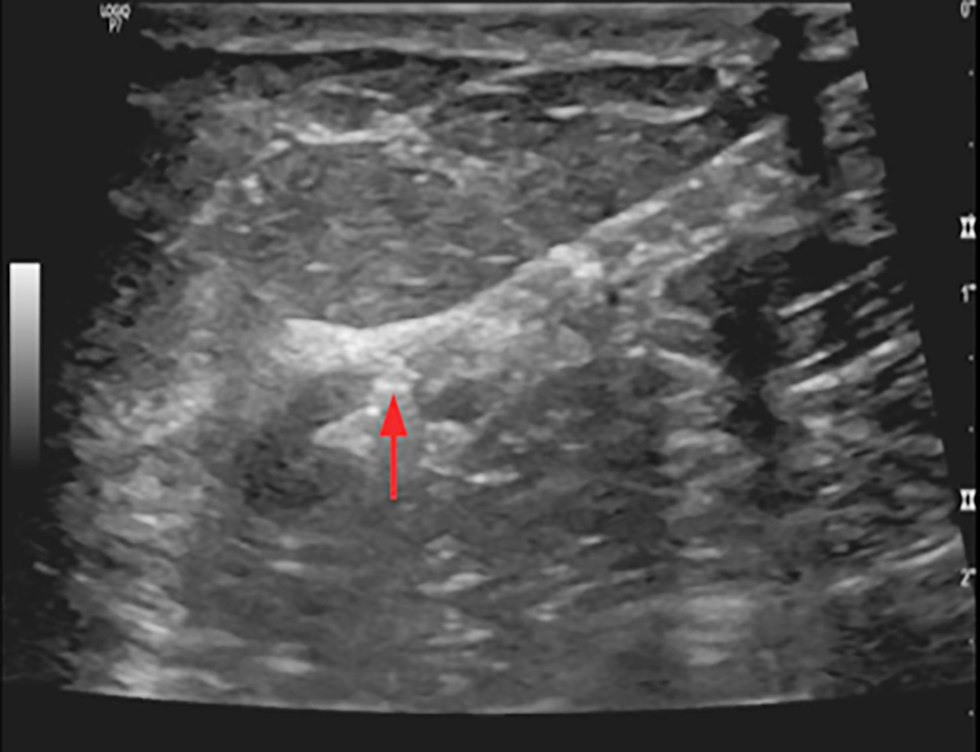

Figure 4 - Ultrasound imaging shows clip inserted in cortex of pathological axillary LN in a female with early breast cancer CN1

For cN1 patients, suspicious nodes underwent US-guided clip placement pre-NAC using titanium clips. Post-NAC, patients with clipped nodes underwent wire localization before surgery under US guidance (15).

The lymph node was submitted for paraffin section assessment to reassess the frozen section results, with management modified accordingly. An example of retrieved clipped lymph node is shown in fig. 1, while clip placement procedures are illustrated in figs. 2, 3, and 4.